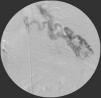

Para confirmar que a malformação vascular detetada era exclusivamente de natureza arterial foi efetuada angiografia seletiva da 4a à 7a artérias intercostais esquerdas que, além de revelar aumento do calibre das artérias intercostais (figs. 9 e 10), demonstrou fístula exclusivamente arterial entre os ramos da circulação sistémica acima referidos e o ramo esquerdo da artéria pulmonar através de novelo arterial (figs. 10 e 11). As artérias brônquicas, nomeadamente as do mesmo lado da malformação descrita, não foram avaliadas angiograficamente.